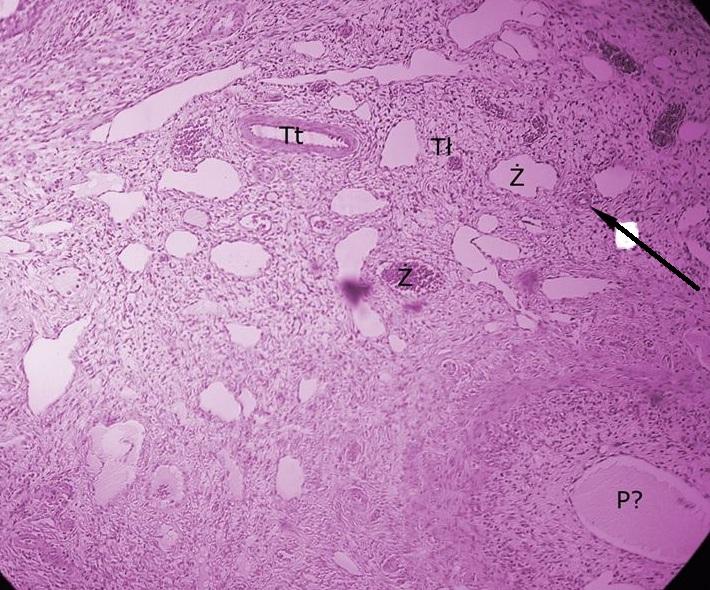

tkanka łączna w rdzeniu jajnika - rdzeń poznajemy po dużej ilości tkanki łącznej i naczyń krwionośnych, a także po braku pęcherzyków (jajnik)

Pytanie 666

tętniczka (jajnik)

Pytanie 667

żyły (jajnik)